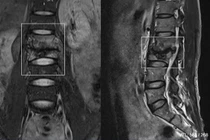

Lao cột sống thường xuất hiện ở đốt sống L1-L2 và D9-D12. Vi khuẩn lao âm thầm phá hủy các thân đốt sống nên ngoài triệu chứng đau vùng đốt sống, người bệnh có thể sốt nhẹ về chiều, chán ăn, giảm cân, cơ thể ốm yếu, mệt mỏi.